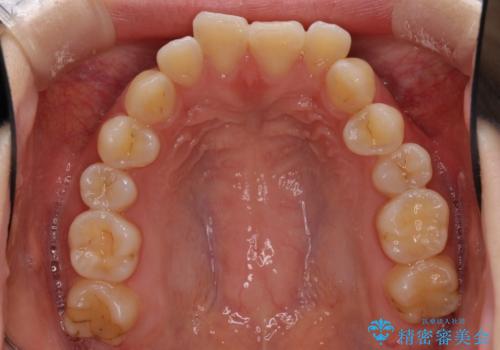

- ハーフリンガル

- 口元の突出感を気にして来院された患者様です。

上下左右の第一小臼歯4本を抜歯して口元を下げる治療計画としました。

裏側矯正特有の抜歯スペースに前後の歯が倒れ込む状態が長く続き、改善に長期間を要しました。